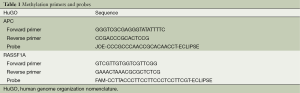

Quantitative methylation-specific PCR

DNA methylation was analyzed by quantitative methylation-specific PCR. All the methylation-specific primes and probes used in this study are designed by Primer Express® Software Version 3.0 and listed in Table 1. DNA extracted from large lung cancer cell line H460 cells was used as RASSF1A and APC methylated or positive control (sequencing confirmed) for the methylation analysis. DNA from healthy volunteers and distilled water were served as an unmethylated or negative control and a blank control. Reaction system content 0.5 μL hot tag, 2.0 μL APC forward primer (5 μm), 2.0 μL APC reverse primer (5 μm), 1.5 μL APC probe (5 μm), 2.0 μL RASSF1A forward primer (5 μm), 2.0 μL RASSF1A reverse primer (5 μm), 1.5 μL RASSF1A probe (5 μm), 10.0 μL 5× buffer, 4.0 μL MgCl2 (25 mm), 2.0 μL dNTPs (10 mm), add ddH2O to 50 μL. The condition was 94 °C for 10 sec, followed by 55 cycles of 95 °C for 5 sec, 60 °C for 34 sec. The standard curve was created by using a series of 1:10 dilutions to calculate the copy numbers of methylated RASSF1A and APC in plasma and serum with concentrations of 150,000, 15,000, 1,500 and 150 copies/mL. The technical triplicates were used in QMSP and at least two positive results could be defined as methylated.

Methylation status of RASSF1A and APC for 89 patients as well as 23 normal samples was examined using QMSP. Representative results of methylation analysis by QMSP were shown in Figure 2, and detailed data regarding the frequency of aberrant methylation were summarized in Table 2.